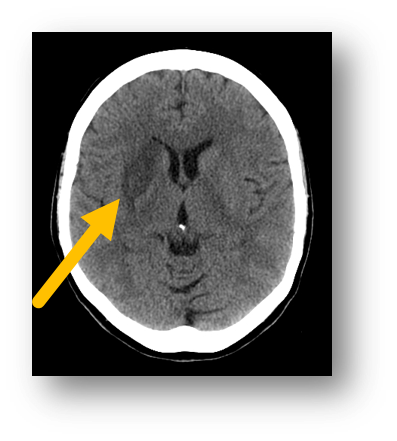

Q

A

hemorrhagic stroke